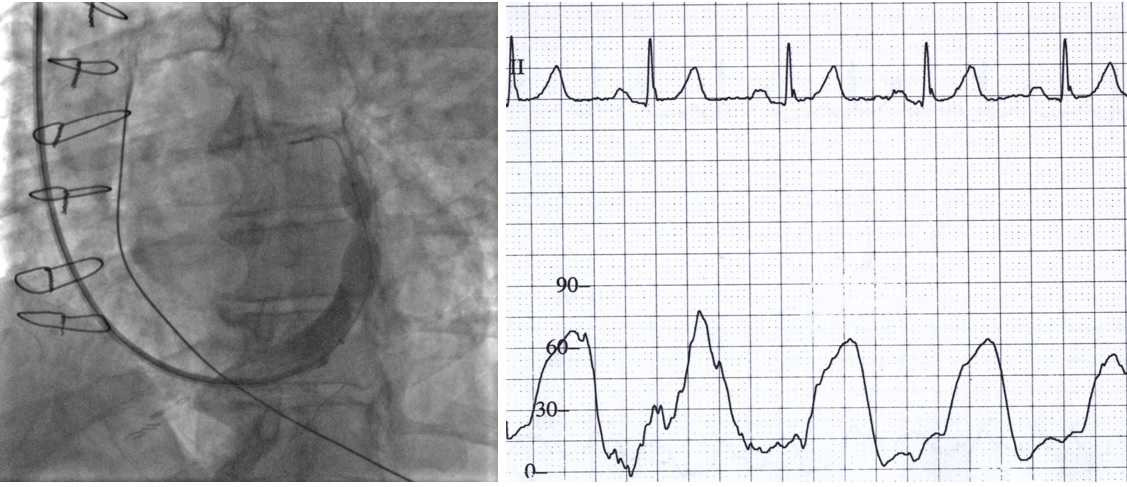

Most patients were male with extensive coronary artery disease. Altogether, 63% of patients underwent previous percutaneous, and 83% underwent previous surgical, revascularization. 83% of patients in the CSR group and 75% in the sham group had a non-revascularized chronic total occlusion (CTO) of at least one coronary artery. The extent of reversible ischemia was comparable between both groups and was primarily confined to the territory of the left coronary artery. All patients were receiving beta-blockers, and 92% of patients were receiving ranolazine. CSR implantation was successful in all patients randomized to the CSR group. Intraprocedural venograms of patients receiving CSR are presented in Fig. 2. Vein tributaries were delineated and allowed distal CSR implantation without visible lateral vein distal to the CSR narrowing. Inferior heart veins were drained to the distal end of the coronary sinus or separately to the right atrium.

Fig. 2.Coronary sinus venograms of 12 patients receiving coronary sinus reducer.